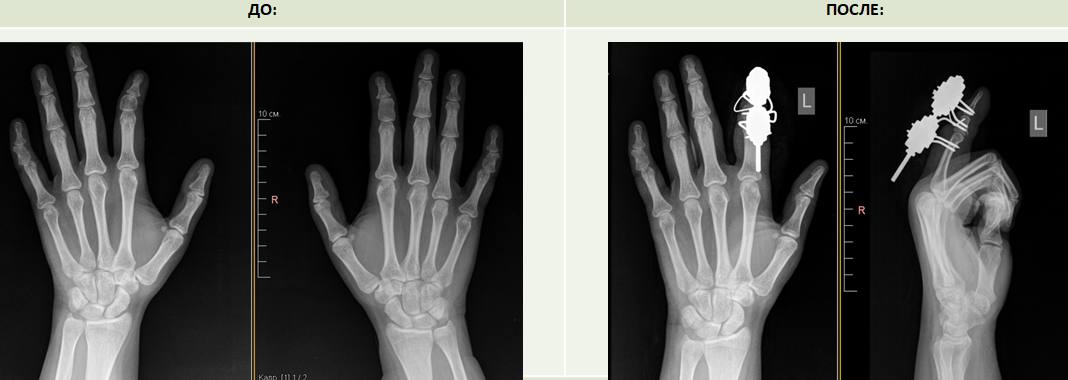

В НМИЦ травматологии и ортопедии имени Г.А. Илизарова обратились сёстры-близнецы с одинаковой патологией кисти. У них один и тот же вид врожденной деформации – клинобрахидактилия.

Патология характеризуется укорочением средних фаланг и угловой деформацией пальцев, у пациенток наблюдались аномальное строение второго и пятого пальцев. У одной из сестёр деформация больше выражена на правой руке, у второй — на левой. Врачи центра впервые столкнулись с почти с одинаковой патологией у двух близнецов.

«Это и косметический дефект и функциональный, потому что указательный палец участвует в основных функциях кисти. В операционной мы устранили деформацию, сделав корригирующую остеотомию, и установили аппарат Илизарова для дозированной дистракции, чтобы компенсировать укорочение фаланг», — рассказала Ирина Чиркова.

Для удлинения укороченных фаланг пальцев по методу Илизарова понадобится в среднем три недели. На период фиксации в аппарате пациенток выпишут на амбулаторное наблюдение.